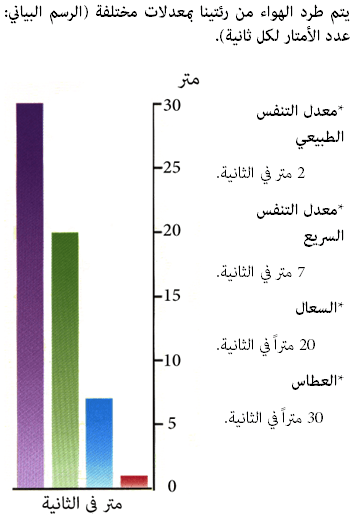

سرعات الهواء